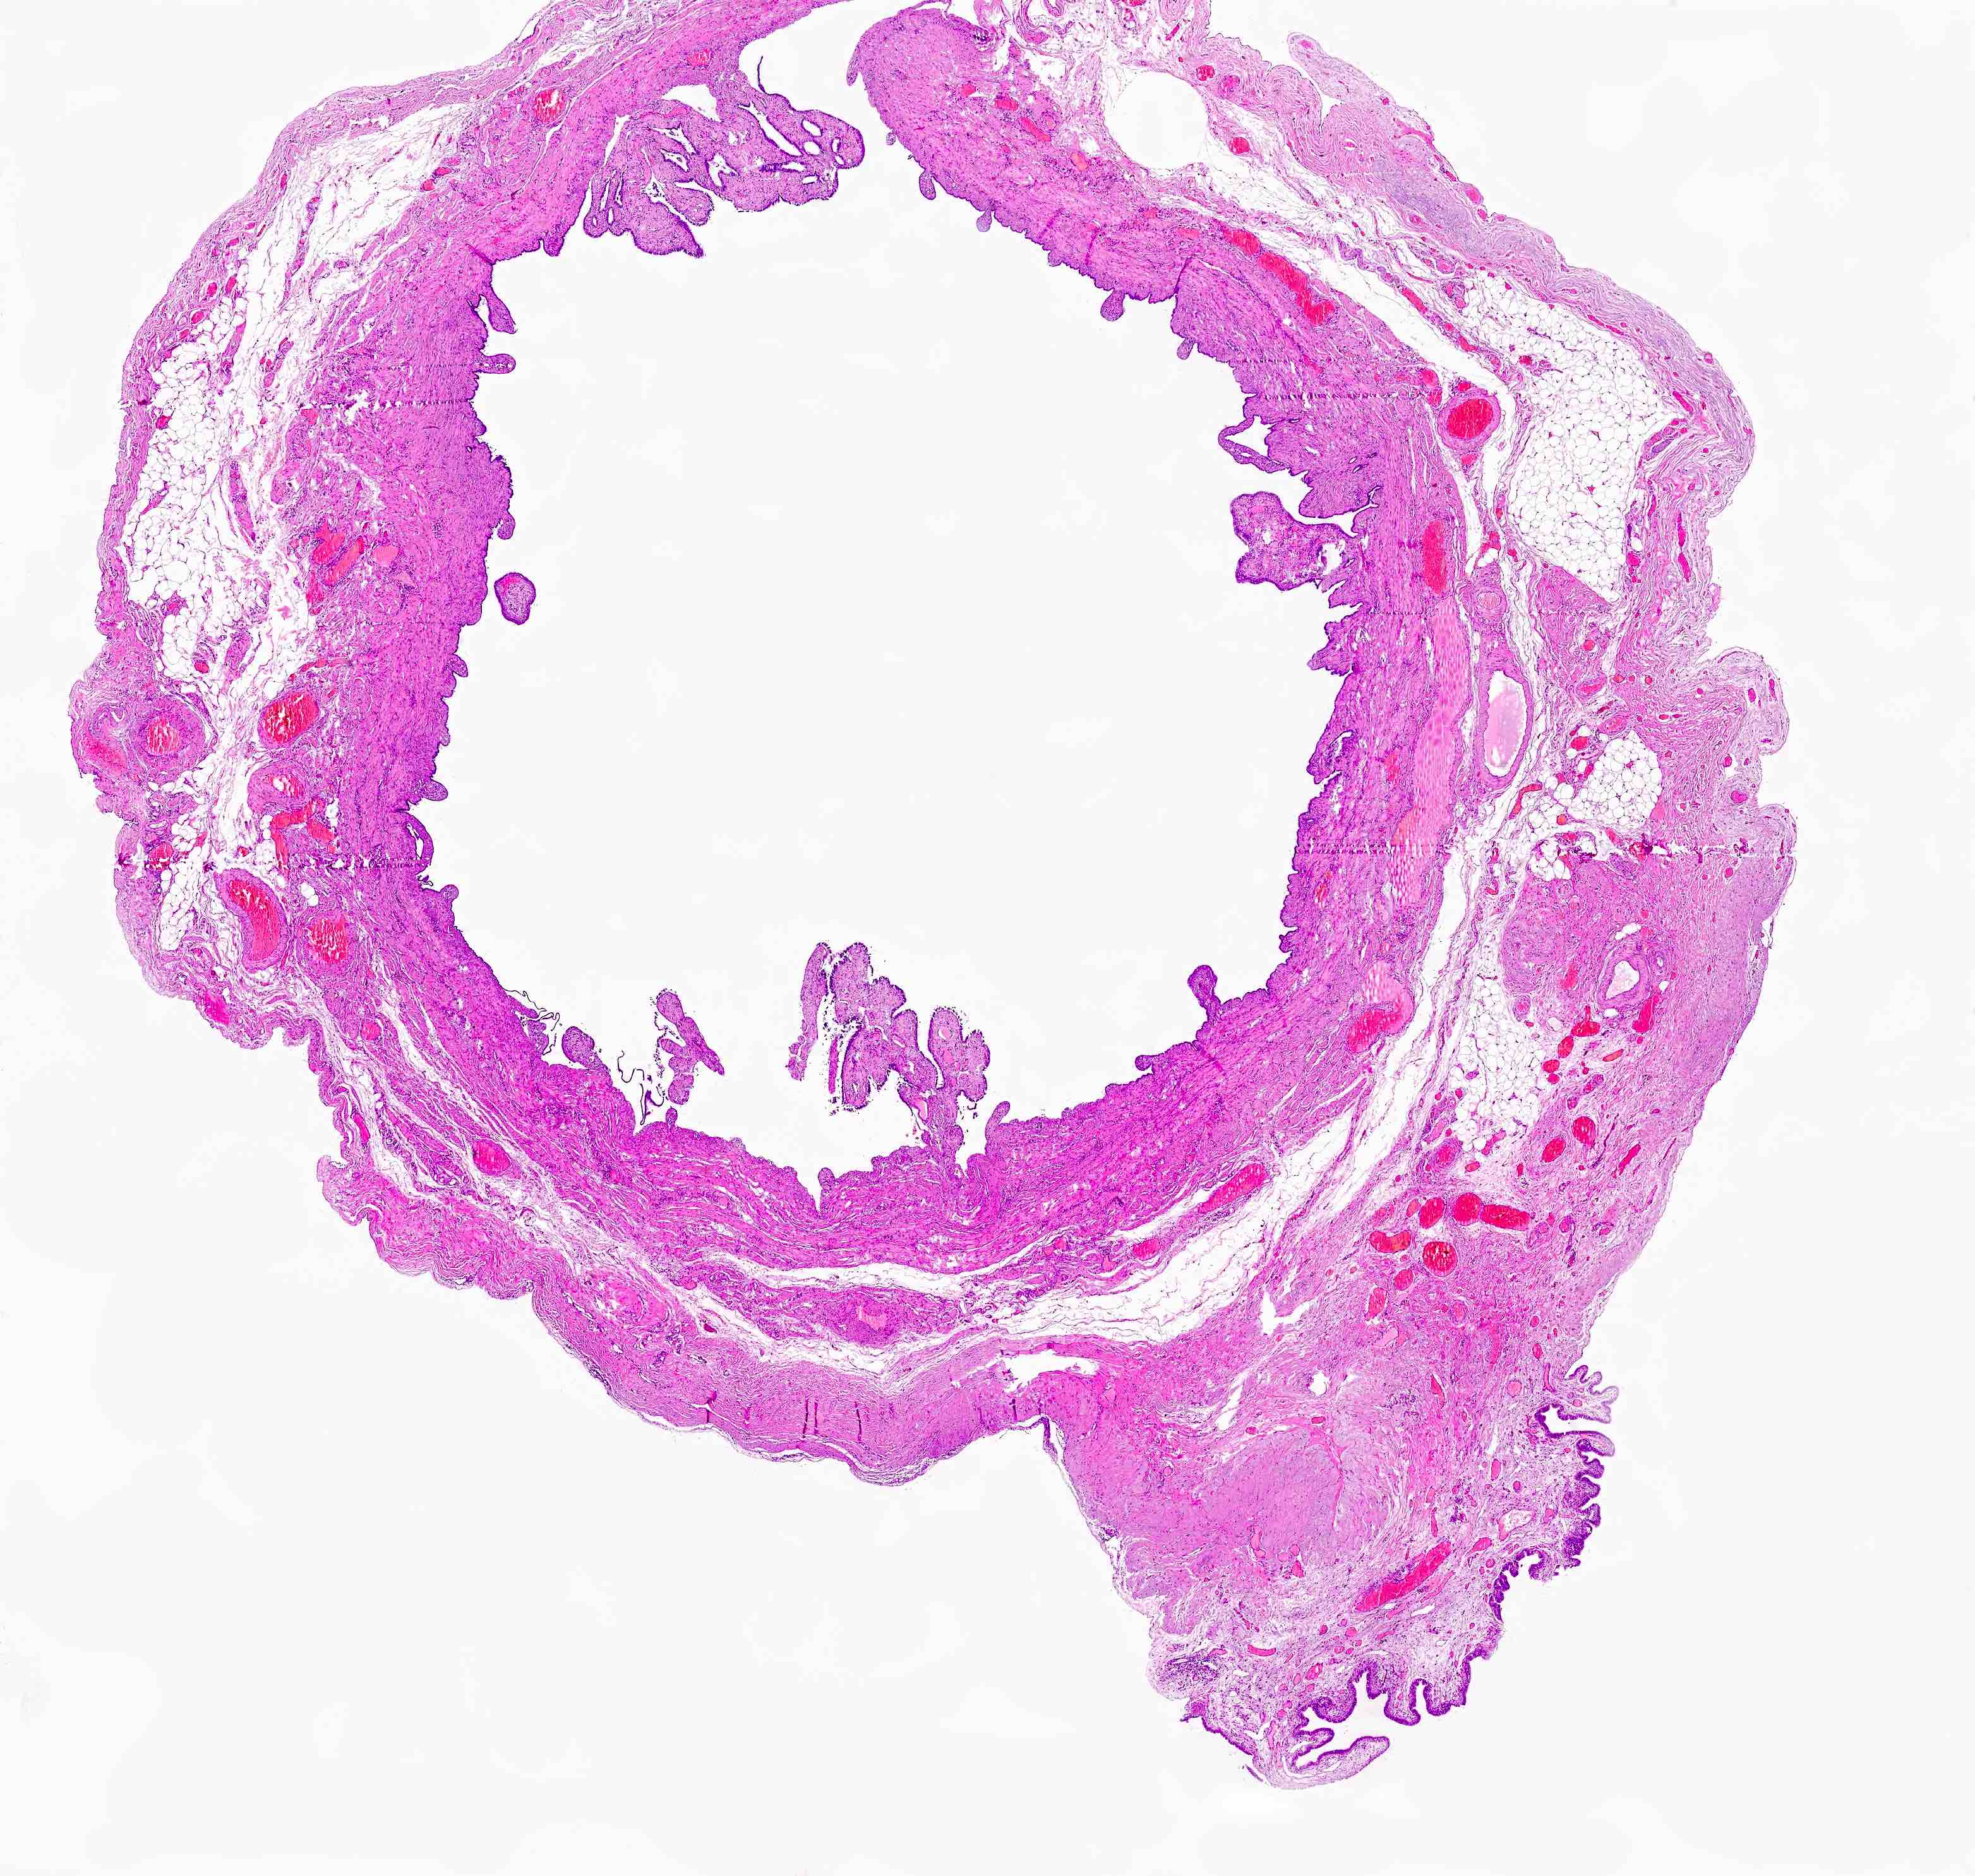

Gross description

- Firm, nodular swellings of the fallopian tube, ranging in size up to 2 cm in greatest dimension (Br J Radiol 2021;94:20201386)

- May be unilateral or bilateral

- Smooth, intact serosal covering

- Cross section of the nodules reveal gray, yellow or brown tissue punctuated by small cysts that surround the original tubal lumen (StatPearls: Salpingitis Isthmica Nodosa [Accessed 22 June 2023])

- Nodosity of the isthmus may give the uterus a horned appearance

Gross images

Microscopic (histologic) description

- Regularly spaced glands lined by normal appearing tubal epithelium surrounded by smooth muscle or fibrous tissue

- Tubal lumina are true diverticula that communicate with the central tubal lumen but do not connect with the serosa